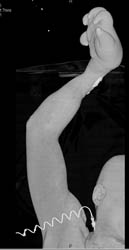

Diagnosis

Pelvic Fracture With Bleed